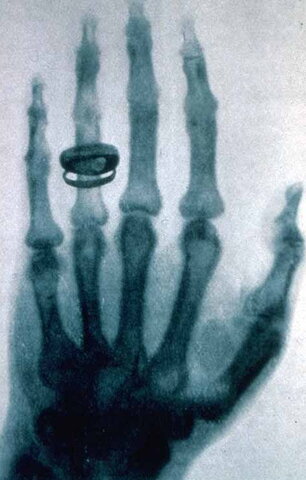

En 1895 fue el descubrimiento de los rayos x por Wilhelm Conrorad Roentgen Científico Alemán que descubrió una radiación de origen desconocido, en aquel momento y de ahí su nombre de Rayos X, la cual tenia la propiedad de penetrar los cuerpos opacos.

En este año, nació el diagnostico medico por imágenes, lo que mejoro la medicina. El 23 de enero de 1896 Roentgen realizo su Primera demostración de los rayos X, ante la sociedad Medica Física de Wartburg.